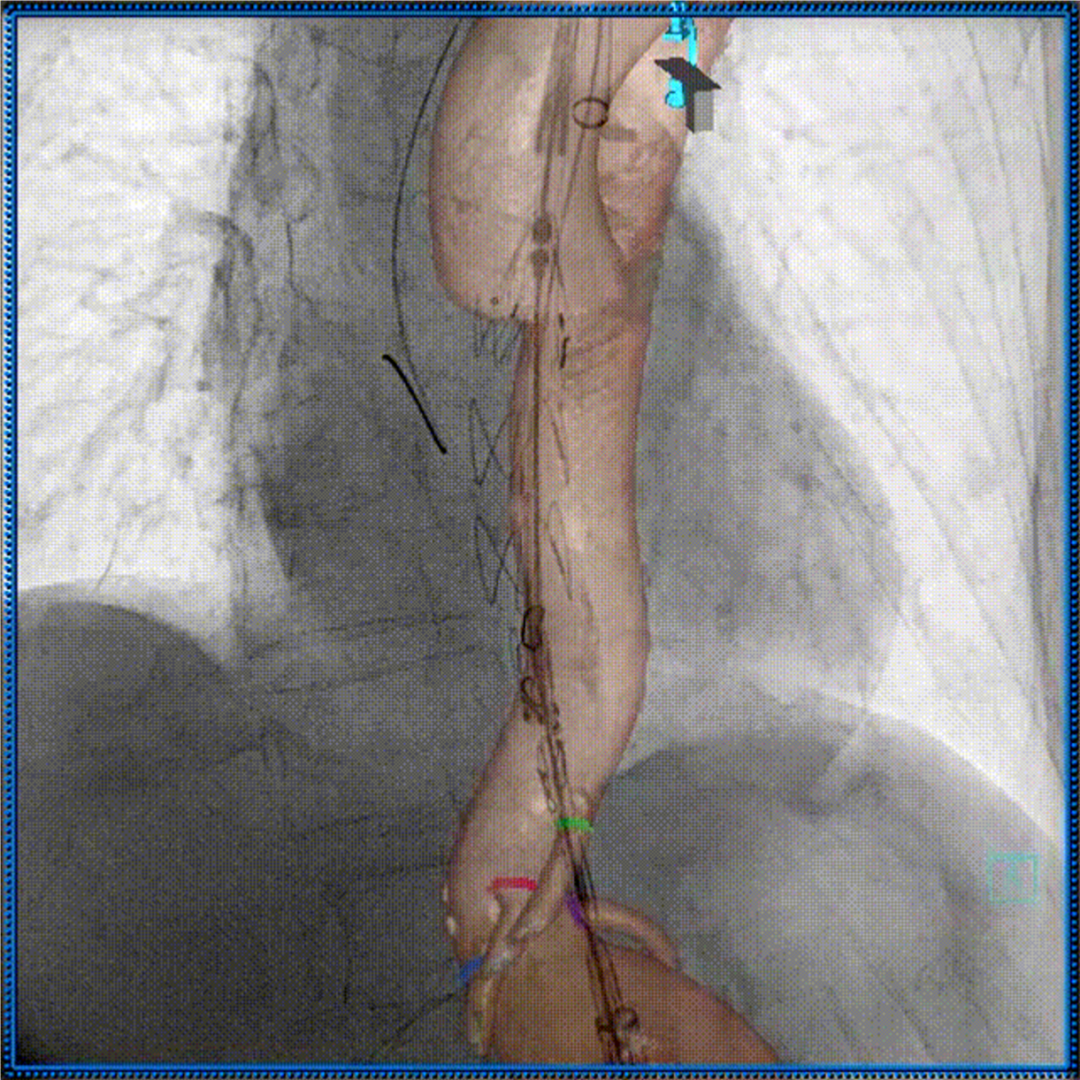

3D影像引导下完成窗口超选、置管及确认

肠系膜上动脉重建

左肾动脉重建

右肾动脉重建

四分支重建后造影,各分支血流通畅